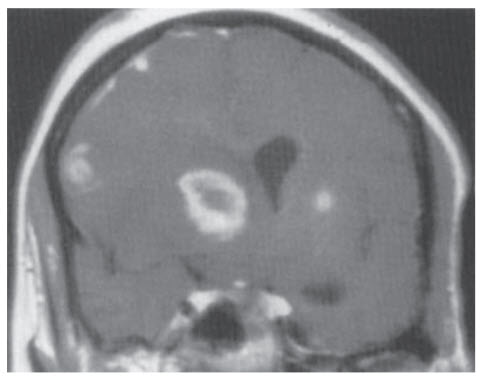

A 45-year-old woman with a history of HIV presents to the hospital with worsening confusion, headache, and fever. She has not been to her physician for follow-up in years, and has not been compliant with her medications. She has been hospitalized twice in the past year for pneumonia. Her last CD4 count measured 6 months ago was 140/mm3 . She is admitted and found to be febrile to 38.6°C. She appears lethargic and vomits several times. Her CD4 count is measured again during this hospitalization and is found to be 76/mm3 . An MRI is performed, and the postcontrast T1-weighted image is shown below.

Which of the following could have prevented this from happening?

A. Azithromycin prophylaxis

B. Yearly cancer surveillance

C. Trimethoprim-sulfamethoxazole prophylaxis

D. Isoniazid and pyridoxine for 9 months

E. There is no available treatment